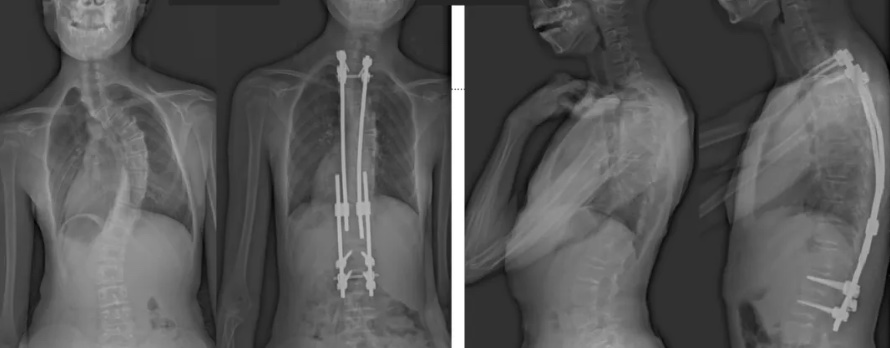

白瑪?shù)恼恍g(shù)前、術(shù)后對比圖(左側(cè));側(cè)位術(shù)前、術(shù)后對比圖(右側(cè))

白瑪今年10歲,正在讀小學(xué)。媽媽發(fā)現(xiàn),白瑪經(jīng)常歪著肩膀,在反復(fù)提醒“站直了,別歪著”后,情況也沒有改善。近半年來,白瑪?shù)挠覀?cè)肩胛骨逐漸向后凸出。到醫(yī)院檢查后發(fā)現(xiàn),白瑪?shù)男刈荡嬖诿黠@的側(cè)凸畸形,是早發(fā)型特發(fā)性脊柱側(cè)凸。由于側(cè)凸較為嚴重,已經(jīng)失去了支具治療的機會。小白瑪才10歲,隨著身體的不斷成長,她的脊柱會越來越彎,肩膀會越來傾斜。這不僅影響體態(tài)和外觀,也可能限制心、肺等內(nèi)臟器官的發(fā)育,導(dǎo)致心肺功能下降、肢體活動不便,出現(xiàn)癱瘓,甚至死亡。對于白瑪這種情況,只能利用手術(shù)治療來矯正脊柱、阻止骨骼畸形進展。

術(shù)后第二天,白瑪就下地活動了。媽媽驚喜地發(fā)現(xiàn),白瑪一下子“長高”了近十厘米,重新抬起了頭,挺直了脊梁,肩膀也不歪了,可謂“脫胎換骨”。媽媽激動地錄制了一段白瑪走路的身影,把喜悅分享給全家。白瑪?shù)男g(shù)后檢查也提示,手術(shù)成功,恢復(fù)良好。